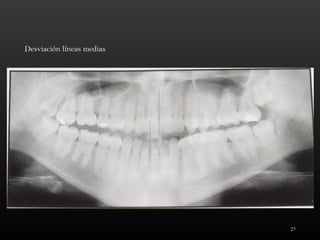

Desviación líneas medias